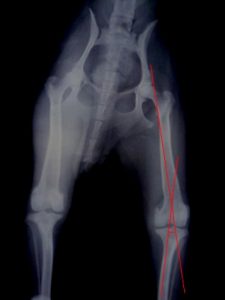

犬膝关节病变矫正手术

犬膝关节病变在临床上越来越常见。易发犬种中,最多见的是小型贵宾犬,卷毛比熊犬,迷你杜宾,京叭等。发病后,有一个最直观的现象,我们可以观察得到,患肢蜷缩,呈三脚跳姿势。

外科手术纠正是解决膝关节病变的一个途径。比如,髌骨内翻,外翻,前十字韧带断裂者。随着临床病例的增加和医生技能提高,手术变得越来越成熟。术后成功率也越来越高。

但是,以髌骨脱位为例,在什么情况下,我们需要做韧带重叠术,什么情况下,我们又需要做滑车再造成形术,甚至是胫骨结节移位术,这里边有着巨大的学问。

我们首先需要掌握的是髌骨脱位的分级。一般是四级。很多教科书和医生的博客里都介绍到了,这里不做过多的重复了。医生根据不同的等级情况来确定动物是否手术,并选择哪种手术。但是有一个问题,髌骨脱位的分级难以界定。每一个分级之间的差距是细微的。这一点在很大程度上影响了医生对动物病情的判断。

有。我们可以用另外一个途径来面对这个问题—Q角。

Q角(quadriceps-angle)  [ˈkwɔ:driseps] 书面语叫股四头肌夹角。它指髂前上棘至髌骨中心点连线与髌骨中心至胫骨结节中心连线所形成的夹角。正常Q角动物约为10°~15°(人的应该在5°~10°)。若Q角大于15°则股四头肌收缩时产生使髌骨向外移动的分力。随着Q角的增大向外侧牵拉髌骨的分力逐渐增大,髌骨稳定性也越来越差。加之在剧烈运动过程中的不确定力,髌骨可游离出滑车沟。所以髌骨脱位很容易发生。

3、胫骨结节移位术

对胫骨嵴生长内旋者,将胫骨嵴移向外移动1~2公分,并用1~2枚克氏针固定。

4、截骨矫形术

如果病犬通过以上方法无效及同时膝关节严重畸形,应实施截骨矫形术,将股骨远端截断,纠正成角,使膝关节与髋关节和跗关节恢复成一条轴线上。

滑车再造成形术有时候会与胫骨结节移位术同步进行。个人认为,对于髌骨内翻,滑车沟过浅者,只要Q角在15°–20°度之间,仅需要加深滑车沟,同时在关节囊外做人造髌内侧韧带就可以了。术后的恢复也应该是比较理想的。